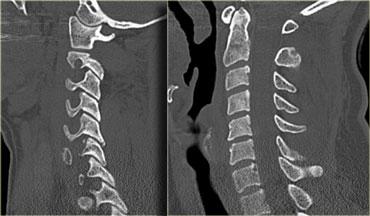

Hình bên trái là hình ảnh của một hành khách 26 tuổi không thắt dây an toàn trong vụ tai nạn giao thông, bị văng ra khỏi xe.

Bệnh nhân có nhiều tổn thương bao gồm tụ máu dưới màng cứng, tràn máu màng phổi, chảy máu ngoài màng cứng tủy sống, gãy cột sống ngực, gãy mỏm ngang L3 trái và gãy xương đòn trái.

Không có thiếu hụt thần kinh khi khám thực thể.

Hãy nghiên cứu các hình ảnh trước, sau đó tiếp tục đọc.

Các phát hiện bao gồm:

- Gãy qua nền mỏm răng

- Phù nề phần mềm trước cột sống

- Đứt dây chằng gian gai C1-C2

- Không quan sát được cột sống cổ thấp

Xem các hình ảnh CT và sau đó tiếp tục đọc.

CT xác nhận các phát hiện trên X-quang và cho thấy thêm hai phát hiện bổ sung:

- Hình ảnh qua phần bên của C2 cho thấy rõ ràng đường gãy đi qua thân C2, tức là gãy mỏm răng loại III.

-

Màng cứng phía sau ở vị trí bình thường, nhưng màng cứng phía trước bị di lệch (mũi tên).